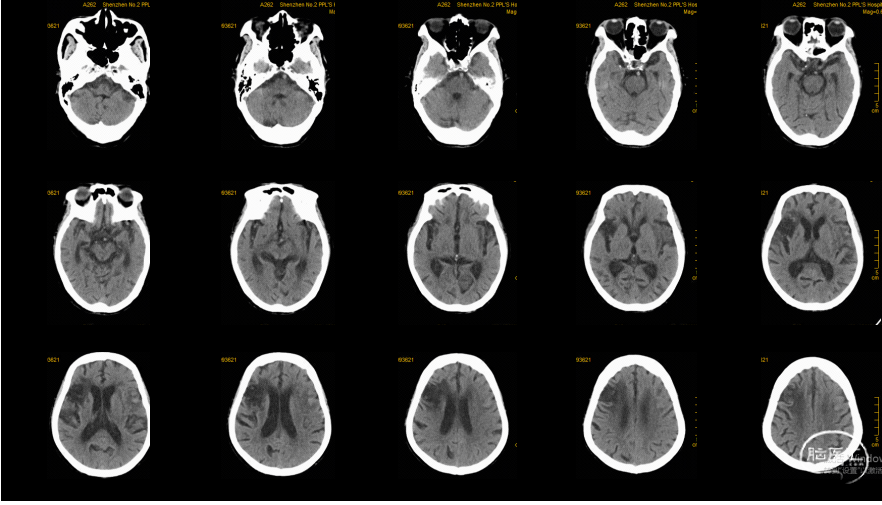

术前CT:

术后8天CT复查

头部多模CT:NCCT